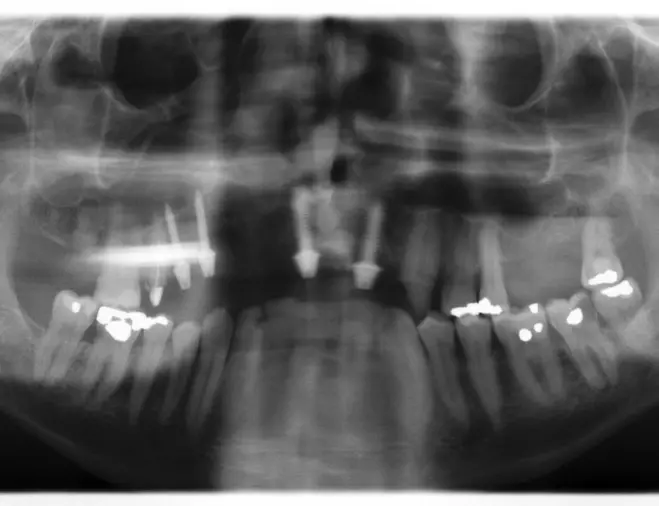

Der Patient war über mehrere Jahre nur unregelmäßig in zahnärztlicher Behandlung gewesen. Aufgrund seiner berufsbedingten zeitlichen Beschränkungen wollte er eine umfangreiche Sanierung seines Gebisszustandes so lange wie möglich hinauszögern. Im Jahr 2008 war zwar eine geschlossene, an eine mikrobiologische Keimanalysenauswertung angelehnte, adjuvante Antibiotikatherapie und Kürettage erfolgt, eine regelmäßige unterstützende Parodontitis-Therapie (UPT) konnte der Patient allerdings nicht einhalten. Im Jahr 2013 führte ihn die Fraktur des apikal beherdeten Zahnes 17 in die oralchirurgische Praxisklinik (Abb. 1 und 2).